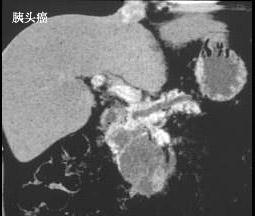

胆总管结石与胰头癌的主要鉴别特点是 ( )A、有无皮肤瘙痒B、有无肝功能改变C、有无淀粉酶改变D、有无肿大胆囊E、有无进行性黄疸

问题 胆总管结石与胰头癌的主要鉴别特点是 ( )

选项 A、有无皮肤瘙痒 B、有无肝功能改变 C、有无淀粉酶改变 D、有无肿大胆囊 E、有无进行性黄疸

答案 E